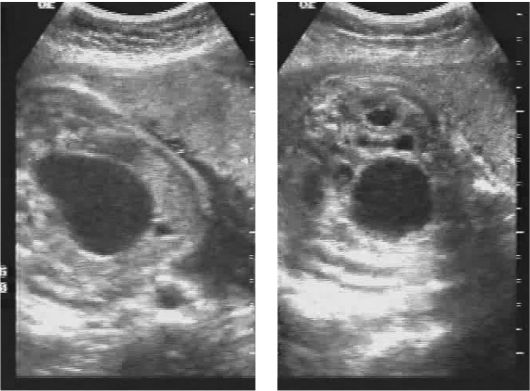

Медицина и диагностика: Инвазивный пузырный занос на УЗИ